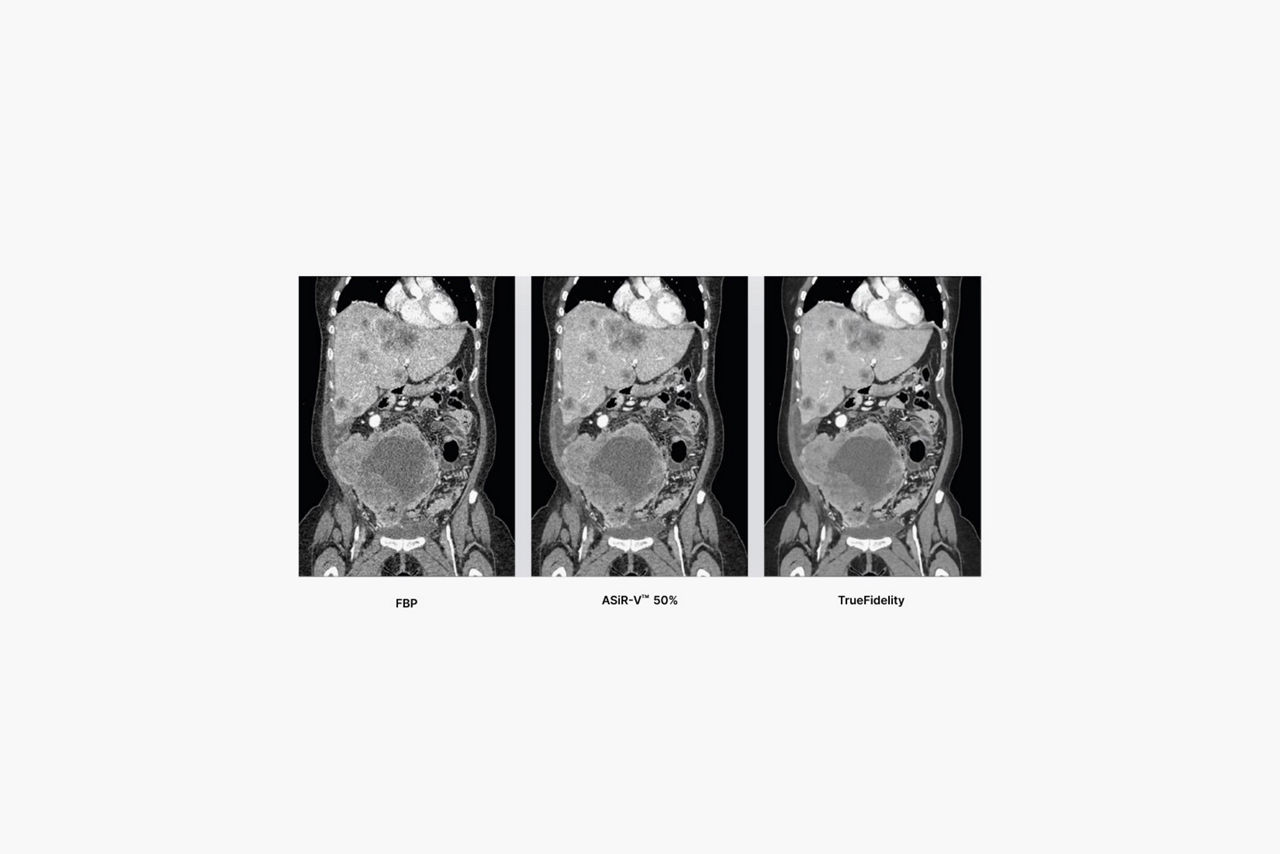

For years, low dose was the benchmark for image quality by which every CT image was held. We helped set the standard for low-dose imaging back in 2008 by introducing the industry’s first iterative reconstruction technology capable of lowering dose. Over the years, the benchmark has changed. While dose is still important, radiologists are looking for an image texture reminiscent of the text-book quality images they studied in medical school.

Take your CT experience even further on a system designed for TrueFidelity, our latest innovation in CT image reconstruction technology that uses a deep-learning based reconstruction engine to combine the low-dose CT you expect with the image texture you want.